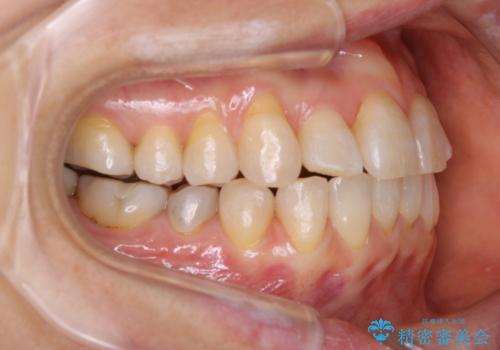

前歯の反対咬合、奥に引っ込んでしまっている歯をインビザラインで治療する

- インビザラインでの治療を希望した患者様です。

上の前歯の反対咬合があり、治療の途中で下の前歯を乗り越える必要があります。

インビザラインでこのような症例を行う場合、乗り越えるのに必要な期間が長くなります。

その為、奥歯で咬みにくい期間が長くなってしまいやすいです。